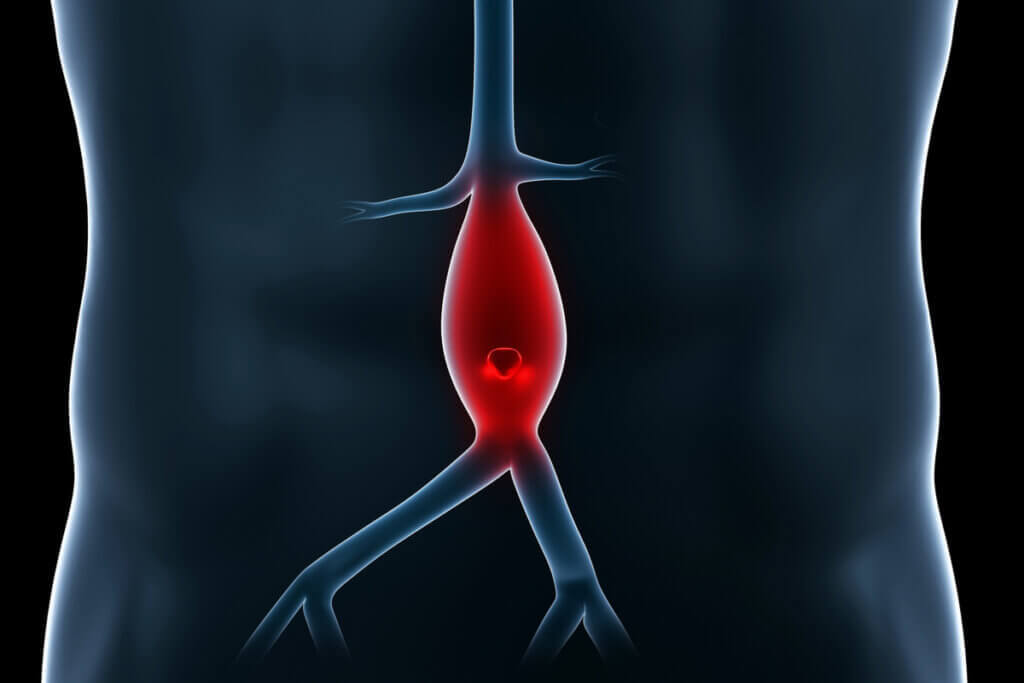

No humano, o sistema circulatório é constituído pelo sangue, por um conjunto de condutos (veias, artérias e capilares, entre outros) e pela bomba motriz conhecida por todos: o coração. É necessário distinguir cada estrutura em um nível fisiológico, uma vez que várias patologias circulatórias variam em gravidade e prognóstico dependendo do local afetado.